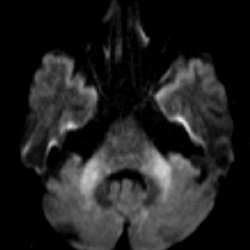

Elia Sechi (@eliasechi) 's Twitter Profile Photo

In our recent study, the "Insular Knife Cut" Sign had 99.3% specificity for HSV encephalitis and was often detectable early after symptoms onset on brain MRI. An ominous sign not to miss in patients with suspected encephalitis of new onset!!! doi.org/10.1111/ene.70…